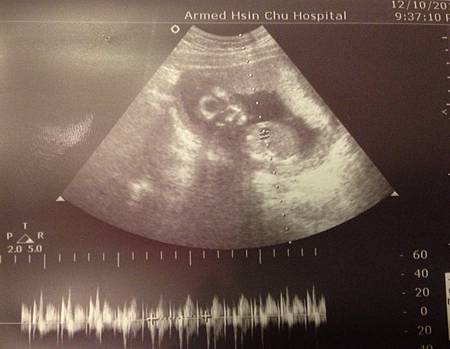

骷顱頭小籠包這次的心跳來到162BPM